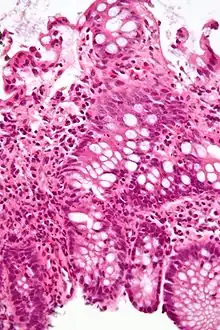

| A micrograph demonstrating cryptitis, a microscopic correlate of colitis. H&E stain. | |

An important investigation in the assessment of colitis is biopsy for histopathology. A very small piece of tissue (usually about 2mm) is removed from the bowel mucosa during endoscopy and examined under the microscope by a histopathologist. A biopsy report generally does not state the diagnosis, but should state any presence of chronic colitis, give an indication of disease activity, as well as state the presence of any epithelial damage (erosions and ulcerations).[6]

Histopathology findings generally associated with chronic colitis include:[6]

Crypt degeneration

Crypt branching and other architectural distortions

Paneth cell (pictured) or gastric metaplasia (only applies in the left colon and rectum)

Other findings include basal plasmacytosis and mucin depletion.[6] Histopathology findings generally associated with active colitis include:[6]

Neutrophilic cryptitis (neutrophils within crypt epithelium)

Crypt abscesses (luminal neutrophilic aggregates)

Gland destruction

Ulceration (seen here as absence of epithelium, and granulation tissue with many fibroblasts)